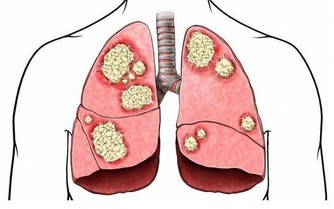

美國夏威夷文明病研究所通過調查5000多位女性發現,每天戴乳罩超過12個小時的女人,

罹患乳腺癌的可能性比短時間戴或根本不戴的人高出20倍以上。